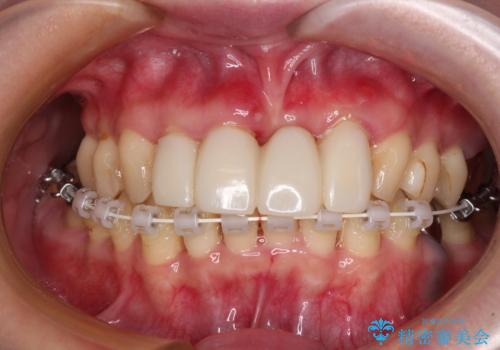

- かかりつけ医にて歯周病治療の名目で治療を行っていたものの、治療プランが明確でないままにインプラント処置を行うとことに疑問を感じ、来院された患者様です。

かかりつけ医では、歯周病治療は終了したため、抜歯を行った右上奥歯にインプラント埋入を行うとの案内があったそうです。

検査を行ったところ、歯周外科処置や抜歯が必要と思われる箇所が散見されたため、あらためて当院に歯周病の初期治療から行うこととしました。

下顎前歯の叢生も気になっており、矯正治療も並行して進めていくこととしました。

自他共に認める、非常に色白の患者様であったため、黄ばんだ歯の色を白くすることを希望されており、歯周病治療の該当部位に限らず、全顎的にオールセラミッククラウンにて補綴治療を行うこととしました。